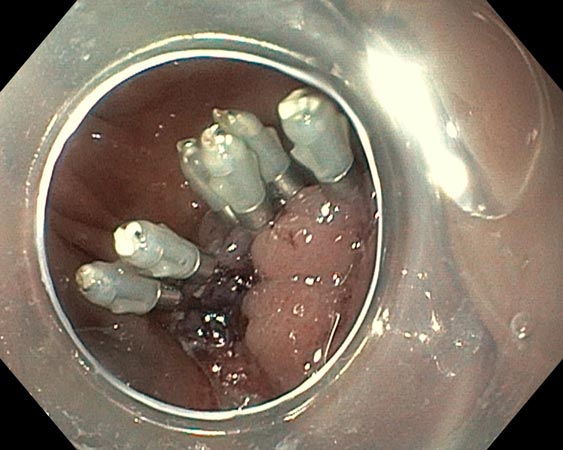

Проводили удаление образования единым блоком для проведения патоморфологического исследования. В случае моноблочной и фрагментарной резекции образования использовали диатермическую петлю SD-210U-25. Сведение краёв клипсами выполняли только после диссекции подслизистых образований (рис. 3–6).

Рис. 3. Частично окаймляющий разрез

Рис. 4. Диссекция в подслизистом слое

Рис. 5. Дефект после удаления

Рис. 6. Клипирование дефекта